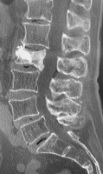

脊椎椎体が骨折しますと一般的には背中が痛みますが、痛みを自覚しない場合もあり、「いつのまにか骨折」ともよばれています。骨折した椎体がつぶれてきますと、背が縮んだり背中が曲がったりします。背中が曲がりますと胃のあたりが圧迫されますので、腹部膨満による食欲減退や食べたものが喉につかえるなどの胸焼け症状を自覚することがあります。

骨粗鬆症がベースにありますので、脊椎椎体骨折が一度起こりますとしっかりと治療をしていない、または医療機関を受診せずに自分で様子を見ていた場合には、別の脊椎椎体が次々と骨折することがあります。これは骨折ドミノとも呼ばれております。

脊椎椎体骨折の治療の目的は、痛みを軽減させること、身体機能を回復させること、潰れてしまった椎体を骨折前の形に近づけ椎体を安定させること、将来の椎体骨折と脊柱変形の進行を予防することです。

治療は原則保存的に行います。痛みが強い時はベッドで安静にしながら痛み止めを内服し、コルセット装着後は痛みに応じて少しずつ動いて頂きます。そして骨粗鬆症の薬物療法を早期より開始します。

ただし、保存的治療で良好な結果が得られない骨折では手術を検討します。骨折した椎体内に骨セメントを充填する経皮的椎体形成術はきわめて侵襲の少ない手術です。全身麻酔でうつぶせになった状態でレントゲン透視装置を用いて行います。背中に2ヶ所小さな切開を加え、骨折した椎体に細い経路を作ります。そこへ小さな風船のついた器具を挿入し、椎体の中に入れた風船を徐々に膨らませ、つぶれた骨を持ち上げて、できる限り骨折前の形に戻します。風船を抜くと椎体内に空間ができますので、その空間の中に骨セメントを充填します。骨セメントは手術中に固まります。麻酔時間を含め、1時間程度で手術が終わります。

骨折ドミノ CT